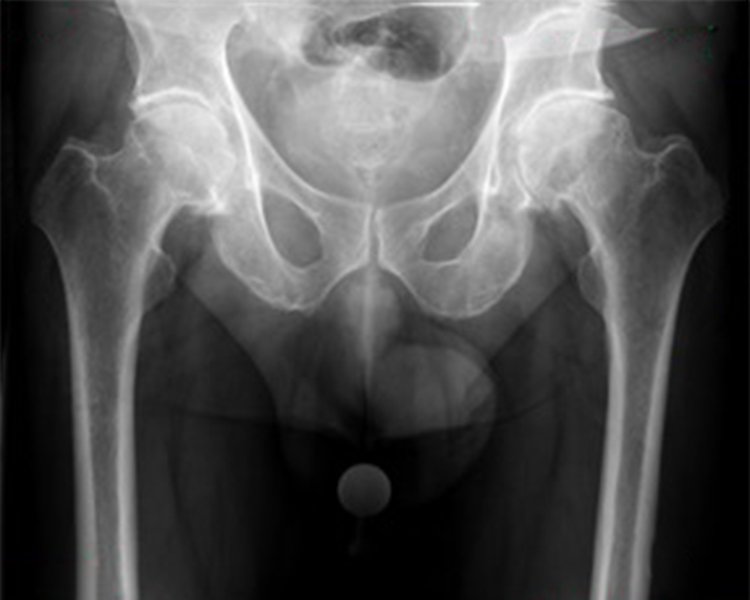

• Fortgeschrittene Hüftarthrose

• Hüftkopfnekrose

• Schwere Verletzungen

• Angeborene Deformitäten / Hüftdysplasie

Eine Hüft-TEP wird empfohlen, wenn konservative Behandlungen (Medikamente, Physiotherapie, Injektionen) nicht mehr ausreichend helfen und Sie unter anhaltenden Schmerzen sowie deutlichen Bewegungseinschränkungen im Alltag leiden. Typische Indikationen sind fortgeschrittene Arthrose, Hüftkopfnekrose oder schwere Verletzungen.